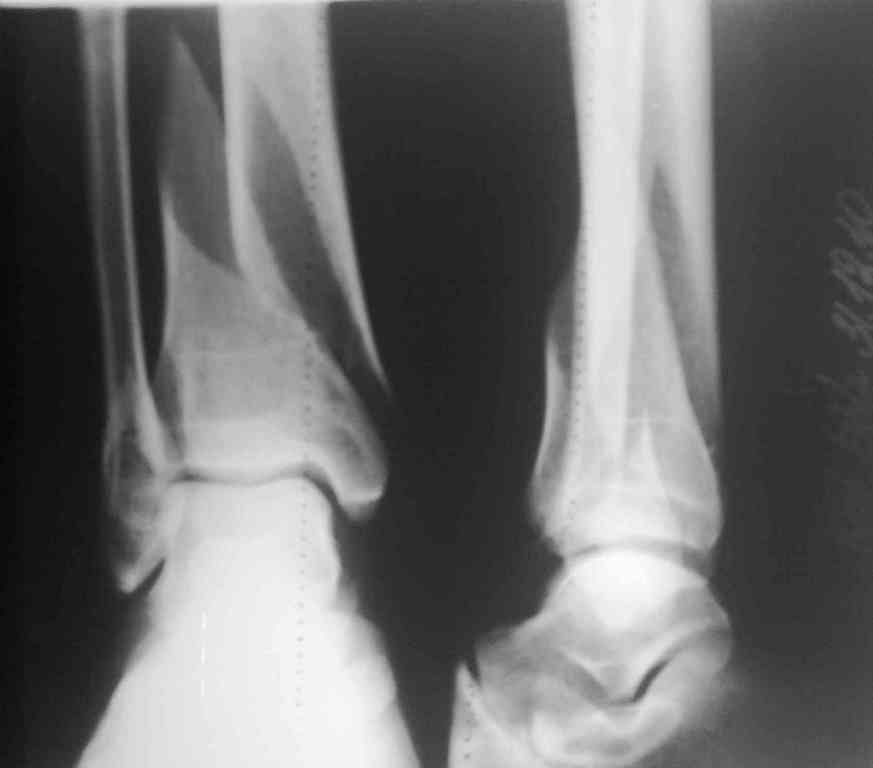

[Ortho] Необходим ли МОС обеих костей голени?

Уважаемые коллеги!На сегодняшнем обсуждении данного клинического примера у нас возникла

дискуссия о целесообразности металлоостеосинтеза латеральной лодыжки.

Предложений несколько:

1)стабильный МОС большеберцовой + гипсовая иммобилицация сегмента 3 - 4 нед;

2)стабильный МОС большеберцовой кости и дальнейшее ведение пациента без внешней

иммобилизации;

3)стабильный МОС обеих костей голени.

Какие у Вас мнения по данному случаю?